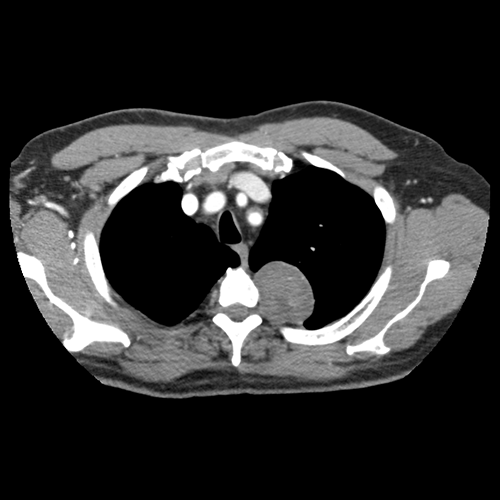

Chest CT

What best describes the findings on the Chest CT?

There is a heterogeneous enhancing mass with enhancing components in the left paraspinal gutter that appears to emanate from the T3-4 intervertebral foramen.

This mass lesion in the paraspinal gutter is most likely a schwannoma arising from a nerve sheath likely arising from a spinal nerve.

Lessons Learned: A posterior mediastinal mass is likely to be a neurogenic tumor. Schwannoma imaging features include a well-circumscribed, heterogeneously enhancing mass.